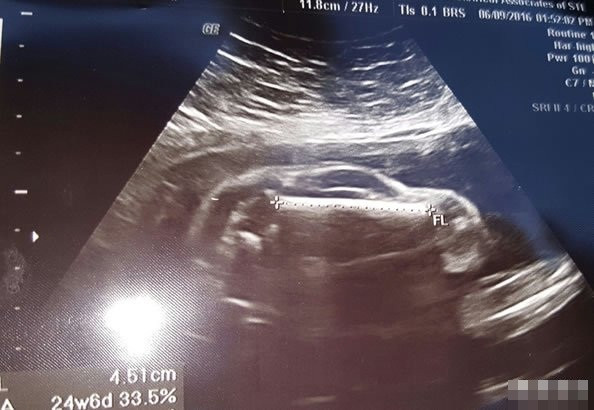

(Kiến Thức) - Trong bức ảnh siêu âm kỳ lạ, hình dáng của thai nhi trông giống như một chiếc xe hơi thể thao. Thậm chí còn rõ ràng đến mức nhìn thấy hình ảnh như bánh xe phía trước và phía sau, cửa kính, phần mui, phần thân sau.

Trong bức ảnh siêu âm của người vợ, có thể thấy rõ ràng cô đang mang thai một em bé kháu khỉnh. Thế nhưng kỳ lạ thay, càng nhìn, em bé càng giống như một chiếc xe hơi thể thao, khiến người cha tương lai vô cùng hào hứng.

Tất cả mọi người đều đồng ý rằng, trong bức ảnh siêu âm này, hình dáng của thai nhi trông giống như một chiếc xe hơi thể thao. Thậm chí hình ảnh còn rất giống các bộ phận bánh xe phía trước và phía sau, cửa kính, phần mui, phần thân sau.

Sau khi xem xong bức ảnh siêu âm này, nhiều người đã để lại bình luận hài hước, cho rằng ông bố này thực sự vinh hạnh khi chưa ra đời, cậu con trai đã ý tứ về một tương lai sáng lạn của mình.